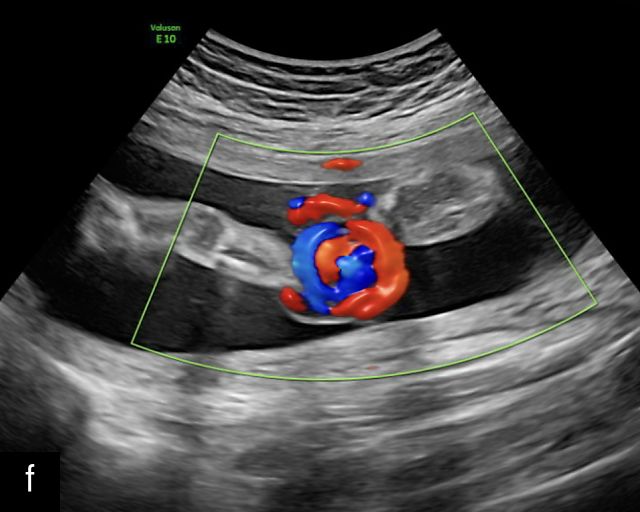

UMBILICAL CORD

Normal anatomy, development and ultrasound appearance

The umbilical cord serves as the lifeline connecting the fetus to the placenta. It arises from the midportion of the fetal abdomen and typically inserts into the center of the placenta (Figure 16). The average length of the umbilical cord is approximately 55 cm (22 inches).185 It contains three vessels: two arteries, which originate from the fetal left and right internal iliac arteries, and one vein, collectively referred to as a three-vessel cord.

Normal appearance of the umbilical cord with two umbilical arteries and a single vein. (a–c) Cross-section of the umbilical cord on grayscale (a,b) and power Doppler (c) ultrasound. In the normal cord, three vessels are visible: a larger umbilical vein and two smaller umbilical arteries. This characteristic appearance is often referred to as the 'Mickey Mouse' sign, the larger circle (umbilical vein) representing Mickey’s face while the smaller circles (arteries) form his ears. (d–g) Grayscale (d) and color Doppler (e–g) images of transverse section of the lower fetal abdomen showing the two umbilical arteries diverging around the fetal bladder. (h) Longitudinal ultrasound view with color Doppler of a normal umbilical cord showing three vessels present in each coil: two arteries with flow in one direction and a single vein with flow in the opposite direction.

The umbilical vein carries oxygenated blood from the placenta to the fetus, while the two umbilical arteries return deoxygenated blood and waste products from the fetus to the placenta for exchange with the maternal circulation. These vessels are surrounded and protected by Wharton’s jelly, a specialized connective tissue derived from the extraembryonic mesoblast, which cushions the vessels and prevents compression. As the umbilical cord approaches its placental insertion, the two arteries form Hyrtl’s anastomosis, a connection that helps equalize blood flow between the arteries.

At a minimum, the mid-trimester ultrasound should include identification and documentation of the umbilical cord's fetal and placental insertions, as well as the number of cord vessels.66,186,187 In a transverse grayscale section of the cord, the two umbilical arteries can be visualized alongside the larger, thinner-walled umbilical vein, creating a characteristic ‘Mickey Mouse’ appearance (Figure 16a–c). Additionally, in a transverse section of the lower fetal abdomen, the umbilical arteries are seen encircling the fetal bladder. This can be seen on grayscale ultrasound and confirmed with color flow Doppler (Figure 16d–g).

A normal umbilical cord is helical, with an average of 2.1 coils per 10 cm of cord length.188,189 The majority of umbilical cords exhibit a leftward (counterclockwise) twist, with a left-to-right twist ratio of approximately 7 : 1, making the rightward (clockwise) twist significantly less common.185,190,191 This twisting structure is believed to provide additional protection against compression and kinking during pregnancy.192